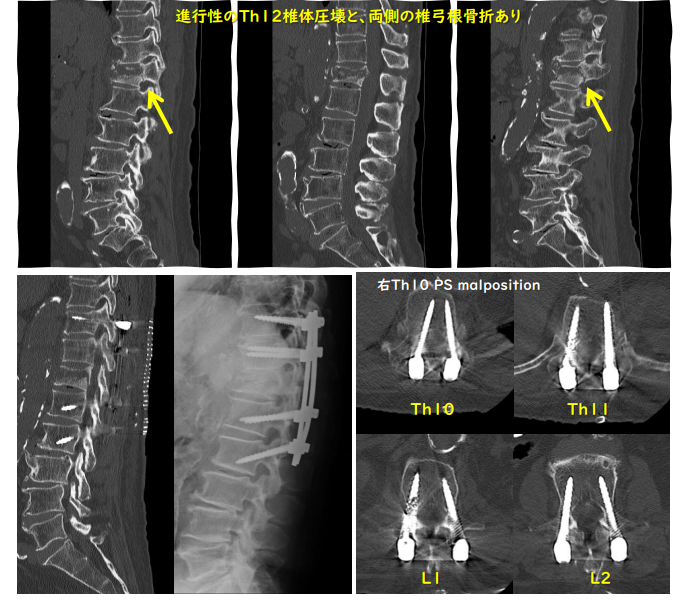

胸腰椎圧迫骨折部の上下の椎弓を露出し、上下2椎体にスクリューを挿入して、圧迫骨折部を安定化します。手術は2~3時間要します。

・神経根障害:スクリューが神経根を損傷する可能性があります。

・スクリューやロッドの破損:手術からしばらくしてスクリューやロッドが折れてしまったり、抜けてしまったりする可能性があります。

・固定範囲外の新たな骨折:固定された椎骨と骨粗鬆症で弱くなった椎骨との強度の差により、新たに周囲の椎骨に骨折をきたすことがあります。